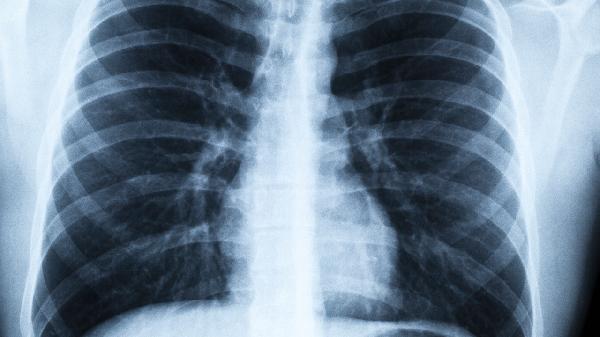

55岁张阿姨最近总觉得右脸颊发麻,起初以为是秋燥上火,直到体检发现肺部阴影。医生拿着CT报告直摇头:“这个位置的肿瘤,其实早就给过面部警.告...”原来某些看似寻常的面部变化,竟是内脏发出的求.救信号。

一、面部异常与肺癌的隐秘关联